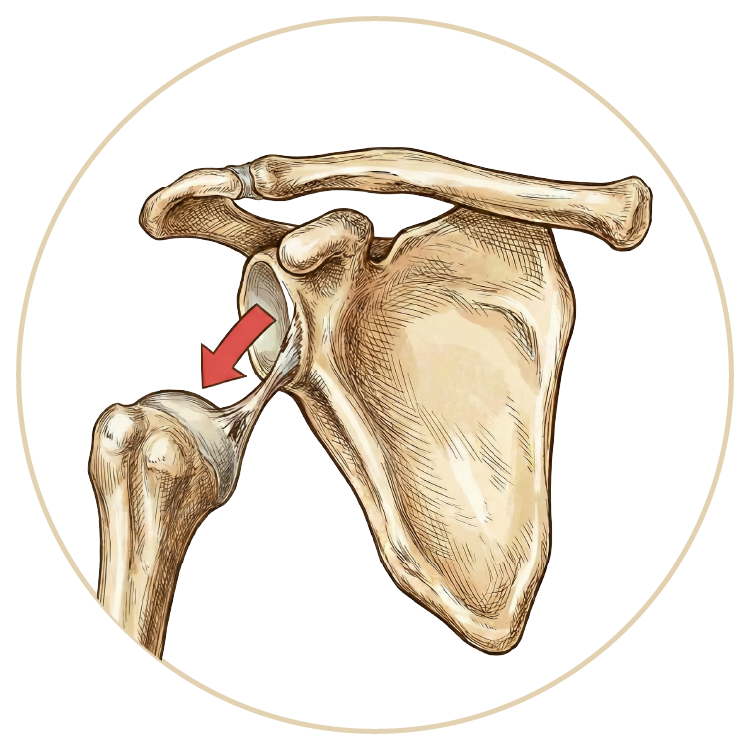

Omuz Çıkığı

Omuz Hastalıkları

Rotator Manşet Yaralanmaları

Omuz Artroskopisi